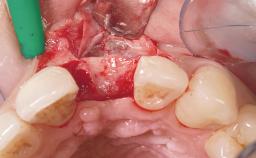

A 36-year-old female patient was referred for the replacement of the upper left central incisor (tooth 21), which had fractured. Although the tooth had been asymptomatic for many years, the crown began to loosen, at which time she presented to her dentist for an assessment. Teeth 21 and 22 had both been endodontically treated many years previously. She was a healthy individual and a non-smoker.

On examination, the patient had a low lip line and only displayed the coronal half of the anterior teeth when smiling.

The crown of tooth 21 was splinted to the adjacent teeth with composite resin, and the gingiva was inflamed.